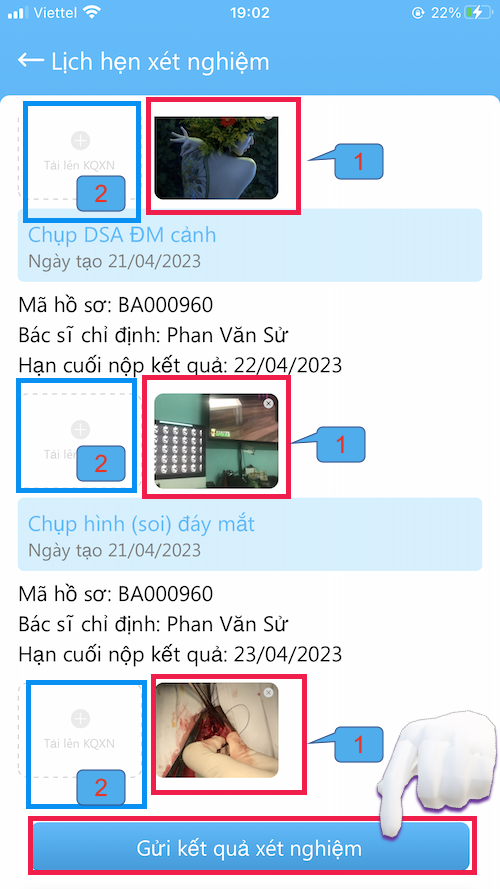

LỊCH HẸN XÉT NGHIỆM

Các xét nghiệm Bác sĩ yêu câù cần làm

- Nơi gởi kết quả cho Bác sĩ

- Các xét nghiệm trước đây cũng có thể xem tại đây

- Gởi kết quả xét nghiệm bằng hình ảnh ( chụp trực tiếp hoặc lấy từ thư viện ảnh)

- Hãy kiểm tra xét nghiệm mà Bác sĩ yêu cầu phải làm

- Trường hợp bệnh nhân chưa nhận được toa thuốc có thể do chưa làm xét nghiệm

GỞI XÉT NGHIỆM

Gởi xét nghiệm cho Bác sĩ

- Vào Tài khoản –> Lịch hẹn xét nghiệm

- Kết quả gởi bằng hình ảnh (chụp trực tiếp hoặc lấy từ thư viện)

- Nên làm theo đúng thời gian hẹn

- Có kết quả, Bác sĩ sẽ gởi toa thuốc

- Vì lý do nào đó, bệnh nhân không làm xét nghiệm, hãy gởi cho bác sĩ nội dung lý do chưa làm (chụp hình chữ viết)

- Bấm Gửi kết quả xét nghiệm khi đã tải hình kết quả lên

- Các xét nghiệm nên trao đổi với Bác sĩ khi khám bệnh

GỞI XÉT NGHIỆM

Gởi xét nghiệm cho Bác sĩ

- Vào Tài khoản –> Lịch hẹn xét nghiệm

- Kết quả gởi bằng hình ảnh (chụp trực tiếp hoặc lấy từ thư viện)

- Nên làm theo đúng thời gian hẹn

- Có kết quả, Bác sĩ sẽ gởi toa thuốc

- Vì lý do nào đó, bệnh nhân không làm xét nghiệm, hãy gởi cho bác sĩ nội dung lý do chưa làm (chụp hình chữ viết)

- Bấm Gửi kết quả xét nghiệm khi đã tải hình kết quả lên

- Các xét nghiệm nên trao đổi với Bác sĩ khi khám bệnh

GỞI XÉT NGHIỆM

Gởi xét nghiệm cho Bác sĩ

- Kết quả gởi bằng hình ảnh (chụp trực tiếp hoặc lấy từ thư viện)

Một kết quả xét nghiệm có thể có nhiều hình

(1) Hình 1

(2) Hình gởi lên tiếp

- Nên làm theo đúng thời gian hẹn

- Có kết quả, Bác sĩ sẽ gởi toa thuốc

- Bấm Gửi kết quả xét nghiệm khi đã tải hình kết quả lên

- Các xét nghiệm nên trao đổi với Bác sĩ khi khám bệnh